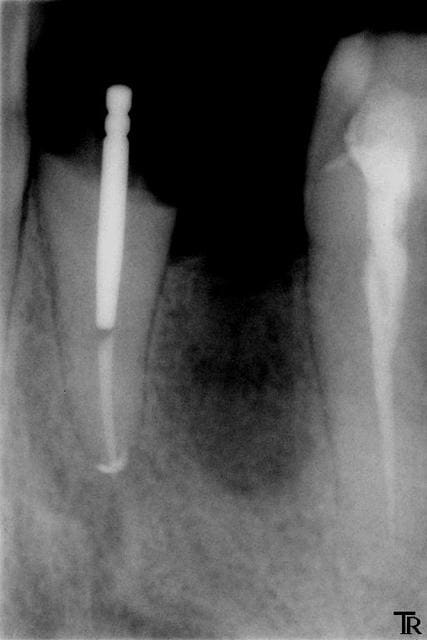

Ce qui me dérange avec les tenons métallique , c est qu'ils ne sont pas anatomiques . Donc il y a très souvent un vide entre la gutta et le tenon (pas de continuum dento prothétique ).

Je prends un calcinable trés sous dimensionné pour me servir de tuteur pour le silicone sans l'enfoncer à fond et le matériaux d empreinte ne se déchire pas (cf photo)